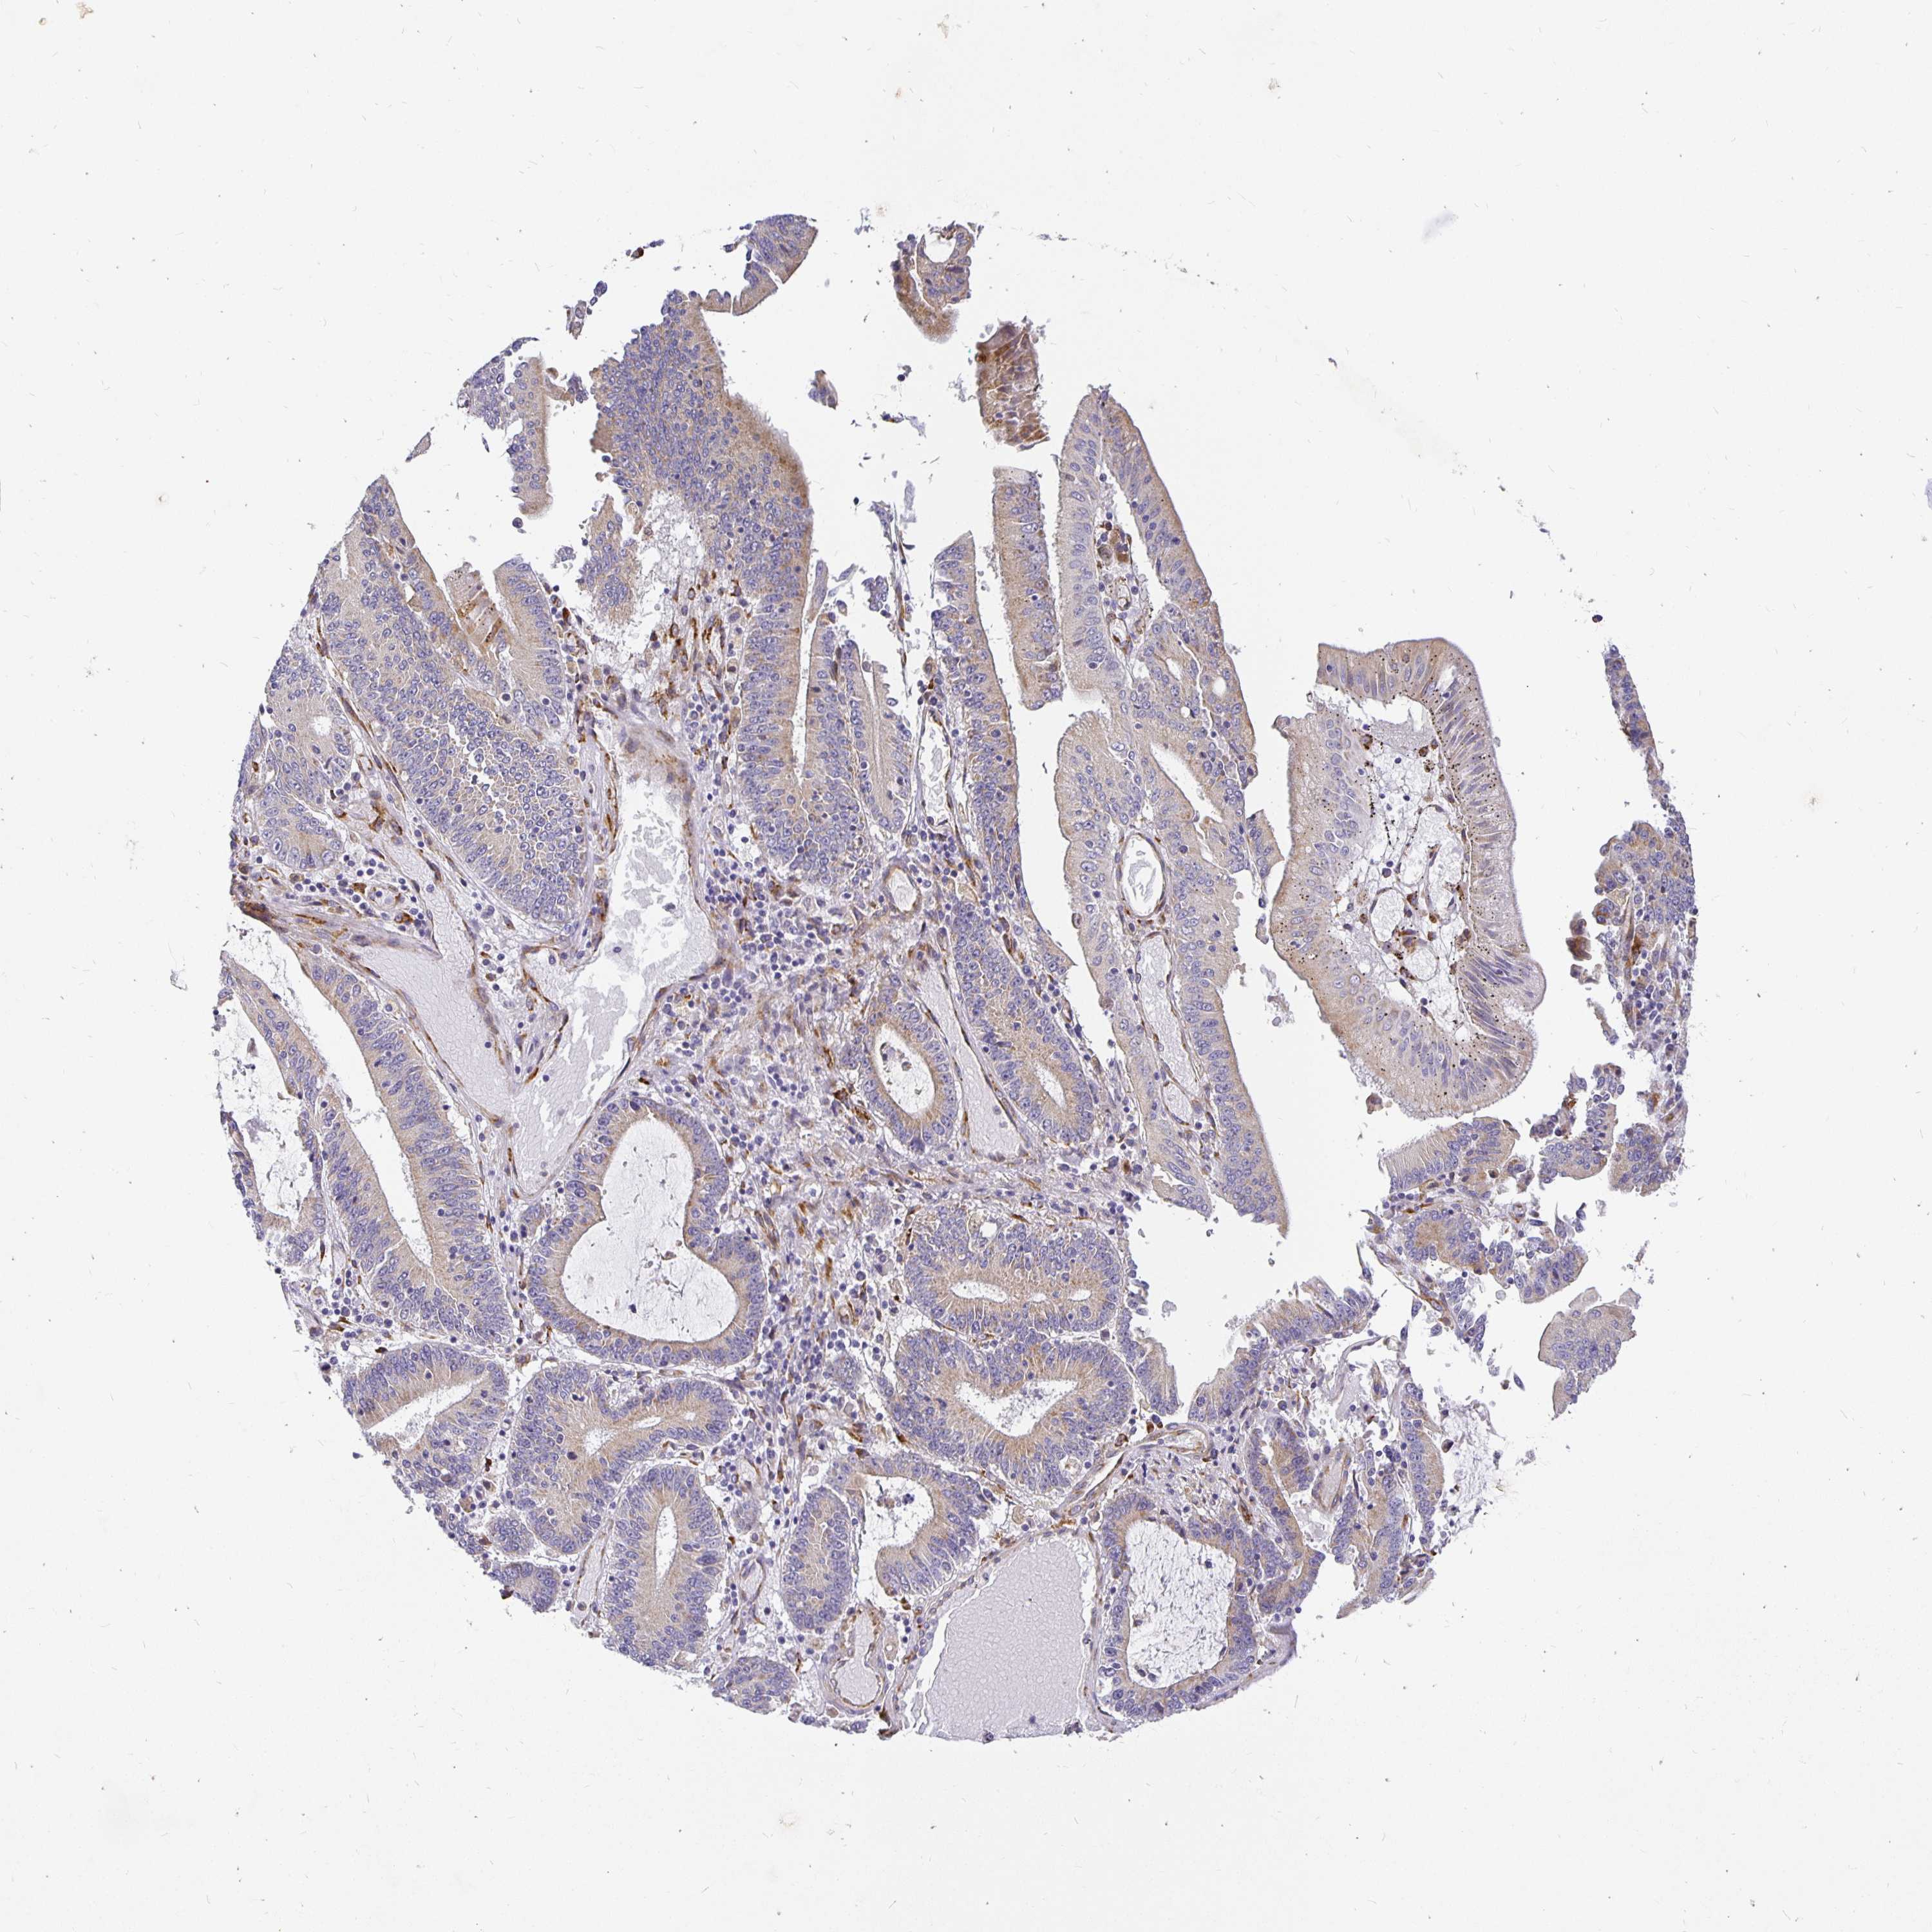

STOMACH CANCER - Protein expressioni

A mouse-over function shows sample information and annotation data. Click on an image to view it in a full screen mode. Samples can be filtered based on level of antibody staining by selecting one or several of the following categories: high, medium, low and not detected. The assay and annotation is described here.

Note that samples used for immunohistochemistry by the Human Protein Atlas do not correspond to samples in the TCGA dataset.

Antibody stainingi

Antibody staining in the annotated cell types in the current human tissue is reported as not detected, low, medium, or high, based on conventional immunohistochemistry profiling in selected tissues. This score is based on the combination of the staining intensity and fraction of stained cells.

Each image is clickable and will lead to virtual microscopy that enables deeper exploration of all samples and also displays staining intensity scores, fraction scores and subcellular localization as well as patient and tissue information for each sample.

Antibody HPA049137

Antibody HPA055799

Staining

High

Medium

Low

Not detected

Intensity

Strong

Moderate

Weak

Negative

Quantity

>75%

75%-25%

<25%

None

Location

Nuclear

Cytoplasmic/membranous

Cytoplasmic/membranous,nuclear

Adenocarcinoma, NOS